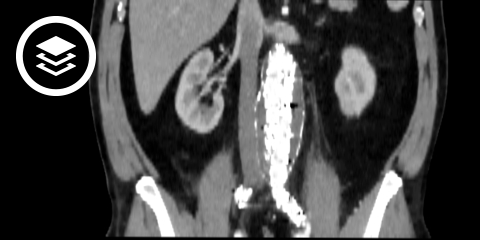

CT-Fallbeispiel

DICOM-Modelle können auf Mobilgeräten leider nicht angezeigt werden.

- Bildquelle DICOM-Viewer: Datensatz freundlicherweise zur Verfügung gestellt durch die Klinik für diagnostische und interventionelle Radiologie, St. Vinzenz Hospital Köln